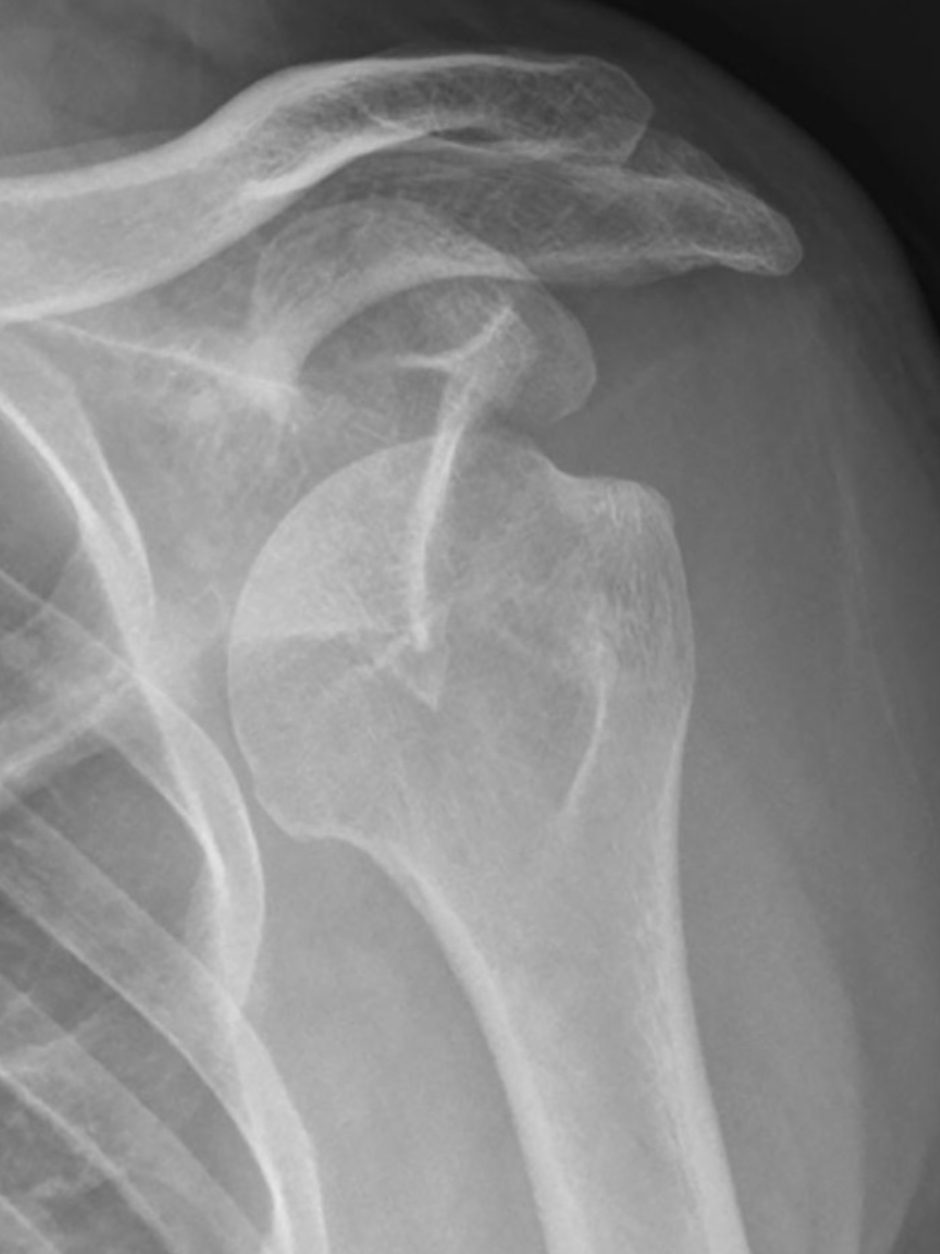

Concentric Arthritis

Eccentric Arthritis